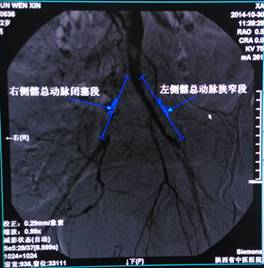

2014年11月04日我院血管病介入科在邓有峰主任带领下,完成一例糖尿病患者右侧髂动脉起始部完全闭塞、左侧髂动脉90%以上重度狭窄的支架植入术。

双侧髂动脉闭塞的发病率在70岁以上的男性中约为1%,在我院属首例。该患者双侧股动脉及足背动脉均未触及,介入操作难度极大。术前经过全科人员积极讨论,大胆创新,确立了合理严谨的手术方案,术中全科人员积极协作,经左侧桡动脉穿刺造影建立路径图,在路径图的引导下完成左侧股动脉的穿刺,从而成功完成双侧髂动脉支架置入术,手术历时仅一个多小时,使患者的双下肢血供得到明显改善。手术过程见下图:

治疗前所见 |